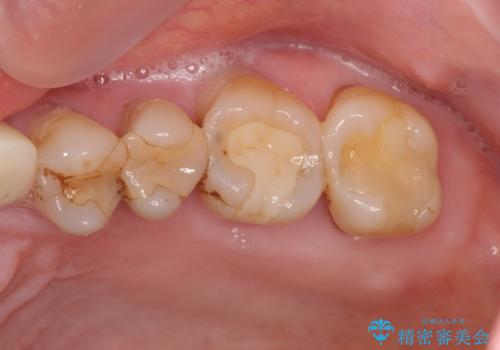

噛み合わせ・歯ぎしりにより、歯周病を発症し感染のコントロール、強い咬合力のコントロールをできるような補綴計画をたてます。

分岐部病変を併発していた歯は、抜歯としインプラントによる咬合機能の回復。残すことのできる歯は歯周治療後連結補綴を行い歯ぎしりに対抗します。

- かみ合わせや歯ぎしりが強すぎる方はセラミックが割れてしまう可能性があります